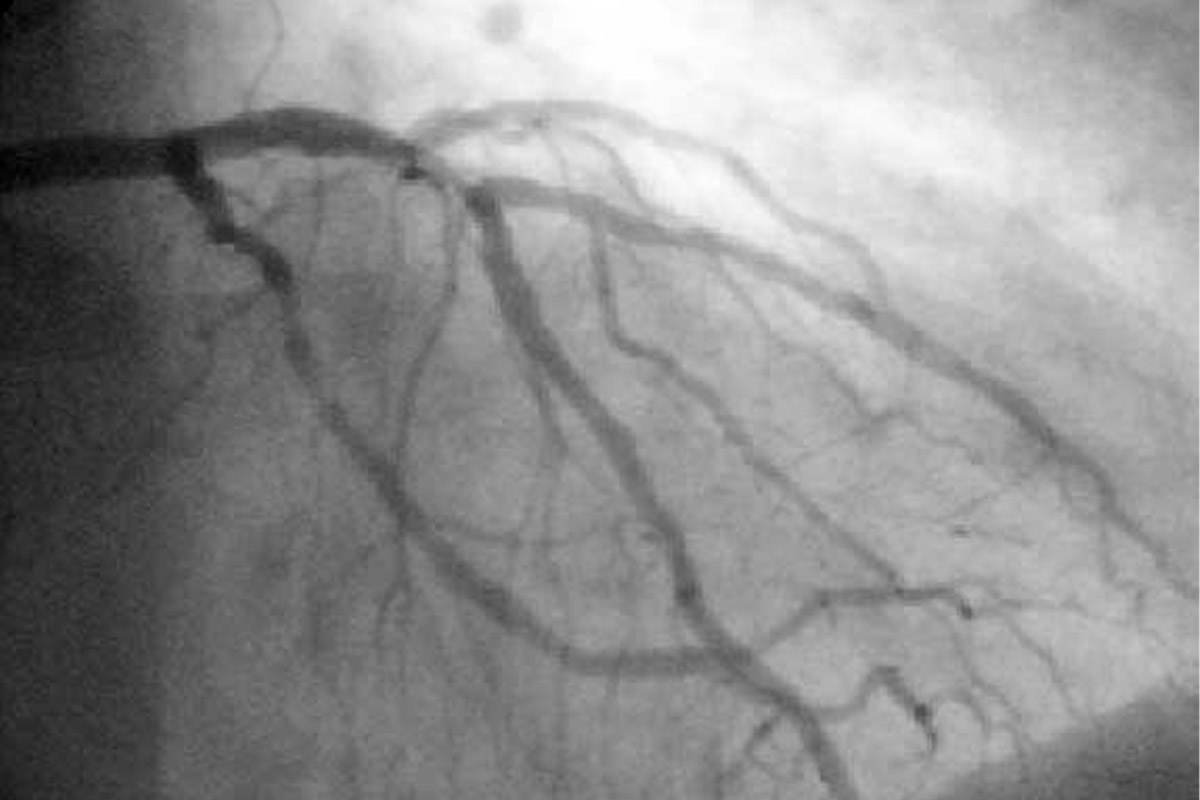

Angiografía coronaria

La angiografía coronaria es un examen de las coronarias bajo rayos X. Este estudio se realiza para analizar si se han obstruido o adelgazado por depósitos grasos llamados placa.